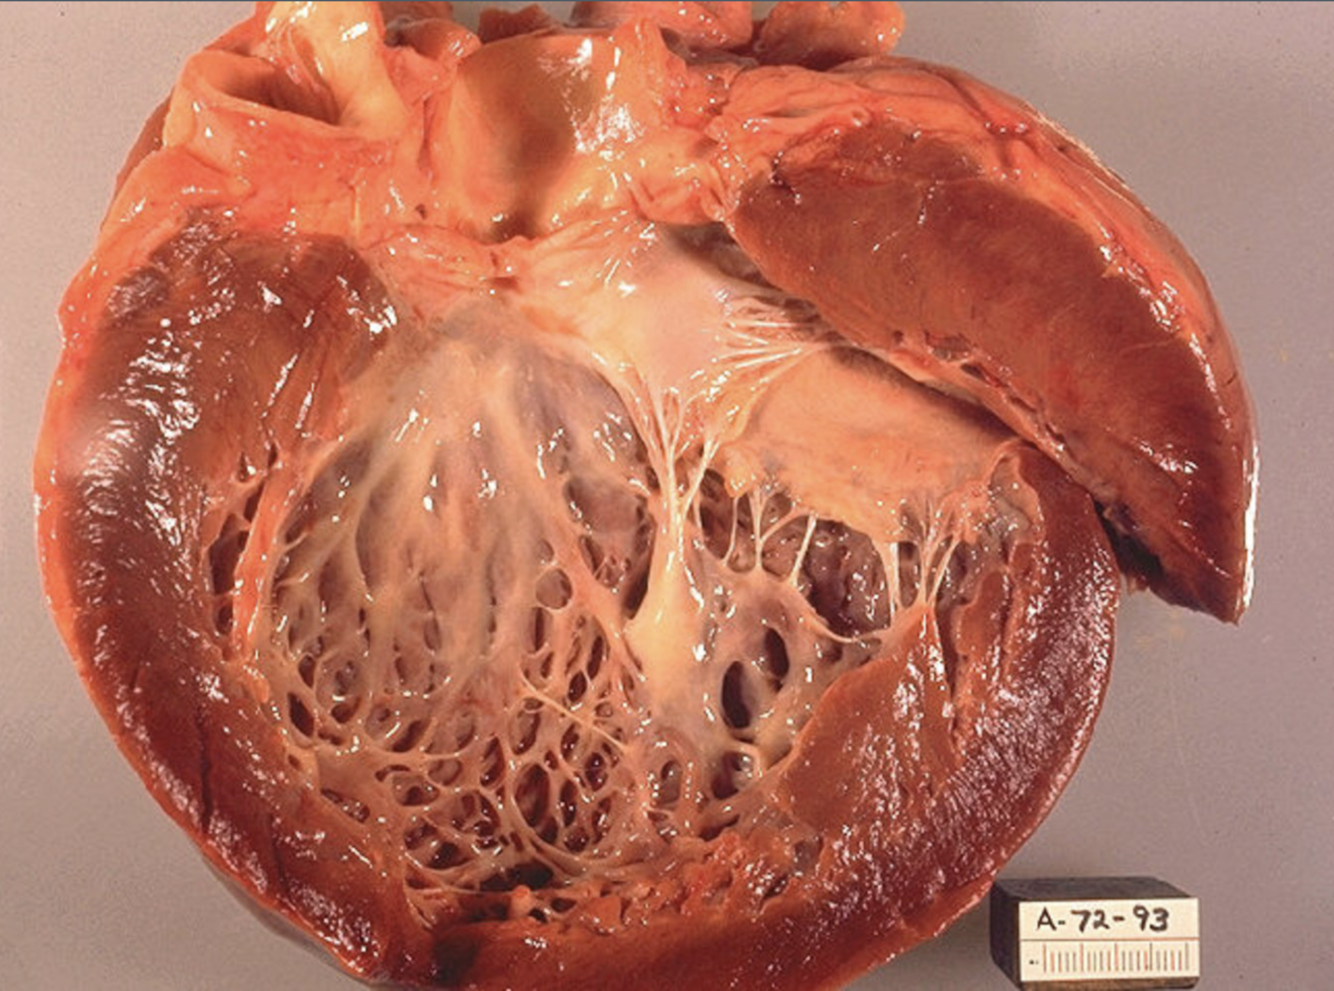

Perfectly

2

Q

What are the cellular components of an atheroscelrotic plaque?

A

1. Macrophages (with injestion of LDL turn into Foam Cells)

2. Lymphocytes (T>B) : involved in inflammatory process and progession of plaque formation

3. Smooth muscle cells